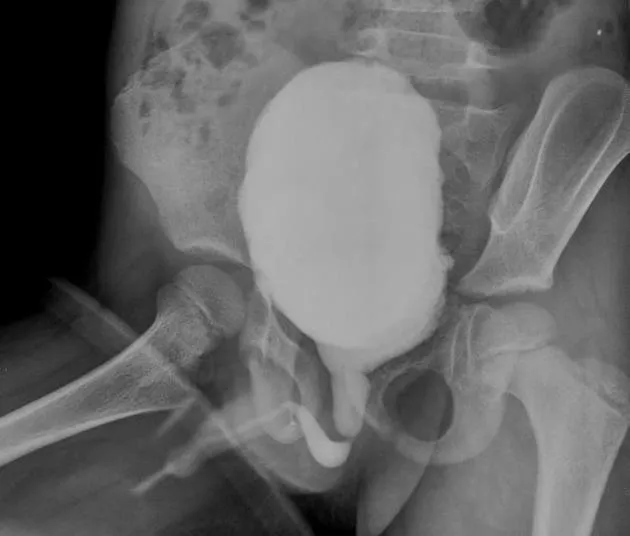

- Posterior Urethral Valves (PUV)

- Males only. Membranous folds in posterior urethra.

- Sx: Poor stream, bilateral hydronephrosis, palpable bladder, VUR common.

- Dx: MCU (key: dilated posterior urethra).

- Rx: Endoscopic valve ablation.

⭐ PUV: Most common cause of bladder outlet obstruction in male infants.